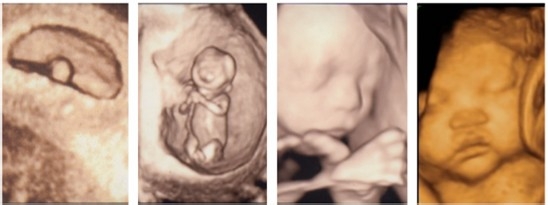

四维彩超室一项超声波检查仪器,是一种声波,它并没有辐射的存在,只是短时间的扫过人体,对孕妇和胎儿并没有不良的影响。四维彩超超声波诊断仪器出色的运用人体工程学设计,不存在射线,光波,电磁波等方面的辐射,对人体的健康没有任何的影响,是一项非常有趣的超声检查。 高清四维彩超不同于传统的三维彩超,三维彩超是立体动态显示的彩色多普勒超声诊断仪。而四维彩超是在三维彩超的基础上,如同放电影一样,展示胎儿即时动态影像。同时,四维彩超在胎儿面部观察方面,能在数秒至数分钟内完成容积数据的采集分析,清楚直观地显示胎儿面部的情况。

四维彩超单胎的最佳时间是孕23-27周(实际孕周)。双胎最佳检查时间是孕22-23周(实际孕周)。因为这个时期的胎儿大小适中,羊水量充足,比较容易采集到相对清晰图像。